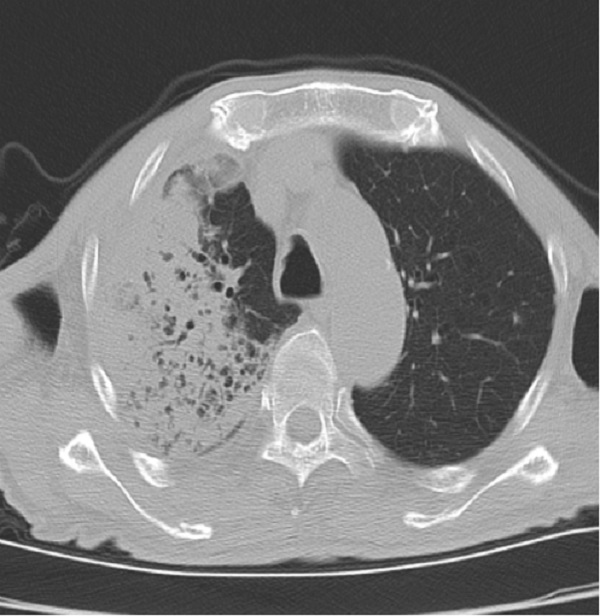

许爷爷今年83岁,不慎摔伤致左髋部疼痛入住二一五医院骨五科,完善检查发现许爷爷新冠病毒检测为阳性,肺部已有感染。由于年事已高,有基础病且合并新冠病毒感染,病情复杂危重,情况非常棘手。骨五科潘建宏主任团队为许爷爷进行了全面细致的病情评估,并请院内相关专家组会诊,制定了有针对性的治疗方案。

入院一周后,肺部感染逐渐得到控制,氧饱和度正常后,潘主任团队为许爷爷进行左侧人工股骨头置换术,手术十分顺利。术后,科室医护人员密切关注老人的神志、呼吸和各项生命体征变化,及时根据病情变化调整治疗方案,并加强肺功能锻炼。术后三天,许爷爷能够在助行器辅助下下床行走,无明显不适,生命体征平稳。在科室医护团队日夜精心的照料下,许爷爷日见好转,说话声音开始响亮,浑身也有了力气,其家属表示深深地感谢,经过半个多月的精心治疗,许爷爷现已康复出院。